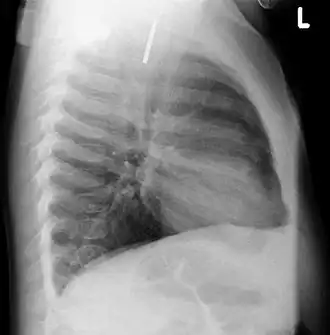

Chest radiograph showing a Venezuelan 25 cent coin lodged in the upper esophagus of a 9-year-old girl. -

A coin seen on AP CXR in the esophagus -

A coin seen on lateral CXR in the esophagus -